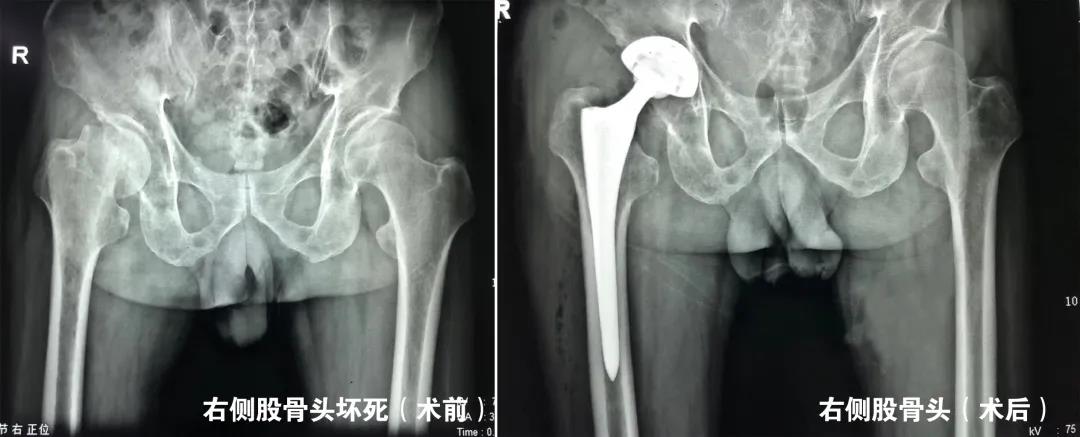

经赵琨主任详细询问病史,并结合影像学检查,确诊为股骨头坏死。赵琨主任向韩先生介绍了目前股骨头坏死早中期的多种保髋治疗方法,并就预后、并发症及相关术后康复锻炼作出详细解答,在与家人经过慎重考虑后,一致同意手术治疗。在赵琨主任主刀下,骨一科团队为其行“双侧股骨头坏死微创减压术”,术中精准减压,手术顺利完成,且创伤小。术后一天,在医生的指导下,韩先生就可以自行活动了。韩先生表示,骨一科的医护人员不仅技艺精湛,为人还很和善,住院期间有啥大事小情,都随叫随到,我们只能用一面锦旗表达内心感谢!

我们根据股骨头坏死的分期不同,根据患者病情“量体裁衣”制定个体化方案,除常规开展微创精准减压治疗股骨头坏死外,对于中末期股骨头坏死即髋关节发育不良导致的继发性股骨头坏死及骨关节炎行全髋关节置换术亦取得了良好的手术效果。